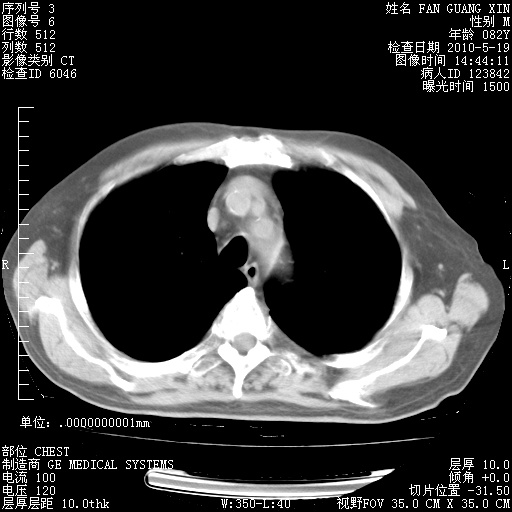

治疗3周后的肺部CT纵隔窗

复查肺部CT,明显好转。为什么发热呢?

治疗3周后的肺部CT